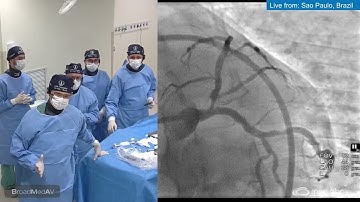

IVUS Guided Complex PCI of Calcified Distal LM Bifurcation